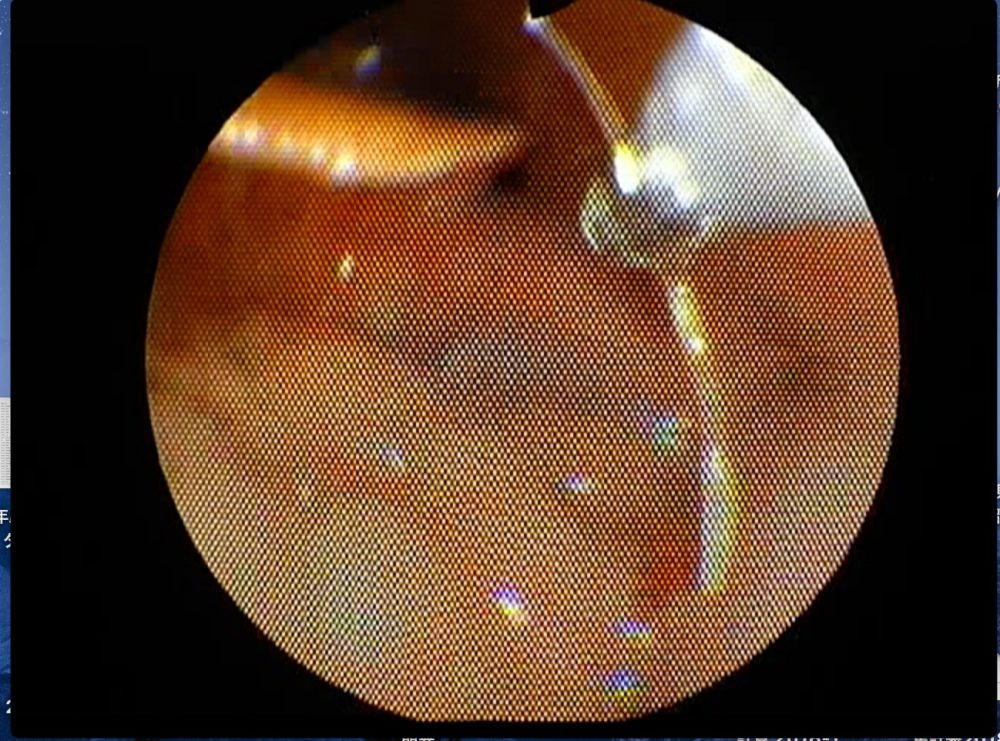

見せる耳鼻科のための、画像ファイリングシステム

小さいお子さんは全例毎回、診察の一部として鼓膜内視鏡の画像を記録しています。これによって、鼓膜のわずかな変化も見逃すことなく、中耳炎を早期に診断して治療をしたり、進行すると怖い先天性真珠腫のような病気を、まだ初期のうちに発見したりすることができます。

それ以外の内視鏡検査や、赤外線眼振検査(めまいの検査)の結果も、すべて患者さんごとに記録され整理されています。

耳鼻咽喉科の領域は、鼻・耳にしてものどにしても、穴の中で普通は見えないところですが、患者さんあるいは保護者の方に、病気のある部分を画像として見て分かっていただく、”見せる耳鼻科”を心がけています。